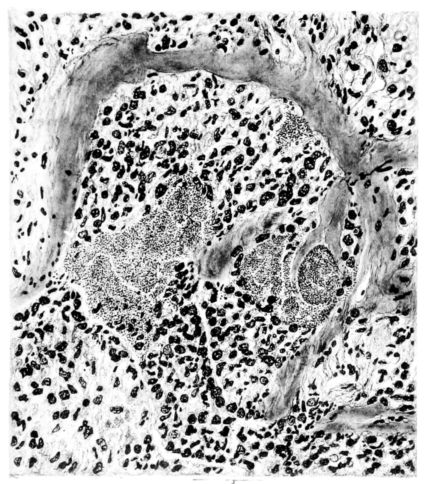

FIG. I. AUTOPSY NO. 99. ACUTE HEMORRHAGIC AND ULCERATIVE LARYNGOTRACHEITIS.

FIG. I. AUTOPSY NO. 99. ACUTE HEMORRHAGIC AND ULCERATIVE LARYNGOTRACHEITIS.

Early in the disease the congestion and the hemorrhages that have been described in the mucous membrane of the nasopharynx (14 and 94) are also conspicuous features in the lining of the trachea and bronchi (Fig. I). This membrane is swollen, turgid, red, and covered by a copious, mucous exudate which may be clear, but much more frequently is blood-stained or opaque and yellowish in color. The blood, variable in amount, may be fresh and red; and after the mucous exudate on the surface is removed, more intense red foci stand out on the congested base (47, 90, 157). Frequently, as the bronchi are approached, the red color of the mucosa becomes more intense and may have a garnet tinge. Membranes such as are encountered in the more usual necrotizing inflammatory processes, like diphtheria, have not occurred in the trachea and larger bronchi in this series (108, 128, 157).[3] The exudate peels off readily, and as indicated above, leaves a velvety red surface, 14dotted here and there with darker or more intensely red foci. Small ulcerations of the mucosa occur, but are inconspicuous (82, 156). As the finer ramifications of the bronchi are approached, the accumulation of the exudate in their lumina becomes more and more marked, and on cross section of the lung, they often stand out conspicuously on account of their increased size and projecting, seromucous, blood-stained content (101, 149, 162).